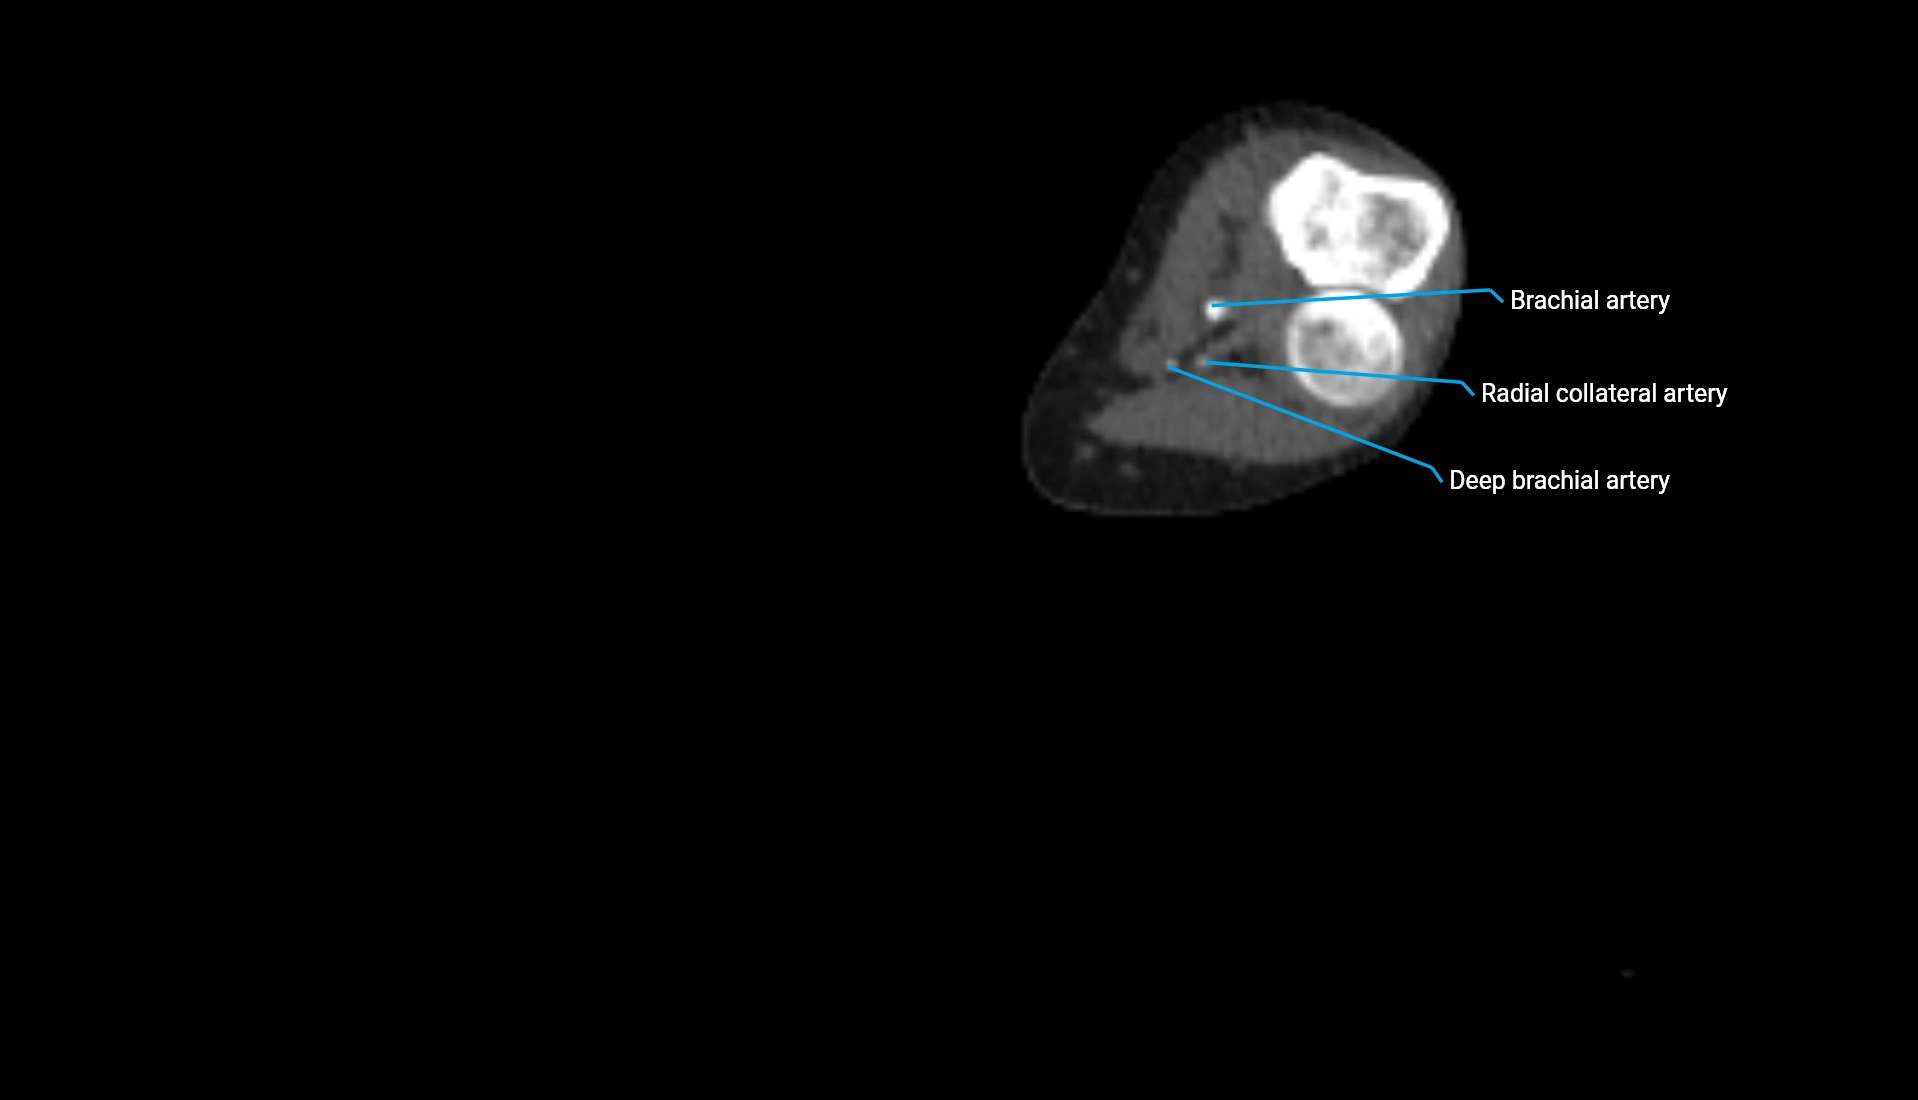

CT Appearance

Non-Contrast CT:

• Cortex: High-density, sharply defined

• Subchondral bone: Dense cancellous matrix

• Articular surface: Smooth concave contour articulating with the capitellum

• Excellent for evaluating bone integrity, alignment, and subtle fractures

Post-Contrast CT:

• Bone: No enhancement

• Joint capsule and synovium: Mild enhancement outlining the joint

• Improves contrast between soft tissues and bony margins

• Useful in detecting subtle joint abnormalities or postoperative changes